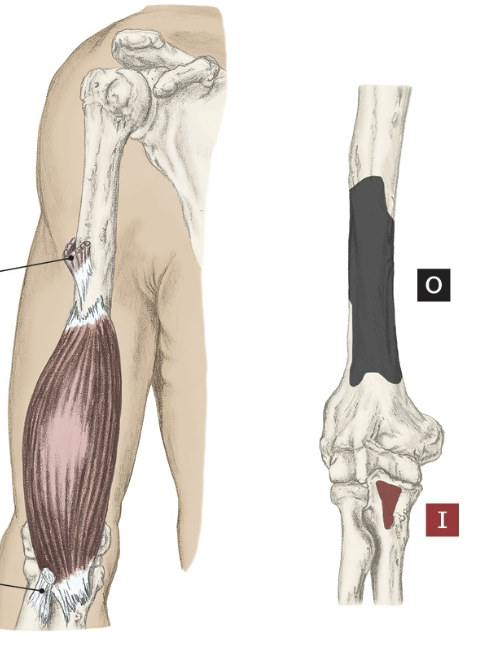

Action of the Brachialis

Elbow flexion

Origin of the Brachialis

Distal half of the anterior surface of the humerus

Insertion of the Brachialis

Coronoid process of the ulna and tuberosity.

Nerve that the Brachialis innervates

Musculocutaneous